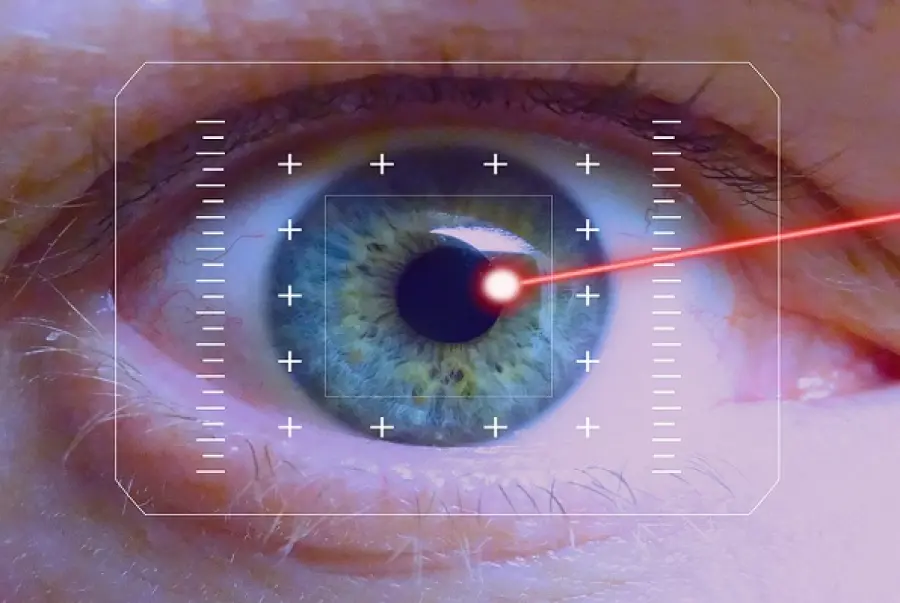

Chirurgia cataratta: approfondimenti e novità

Redazione - October 18, 2019